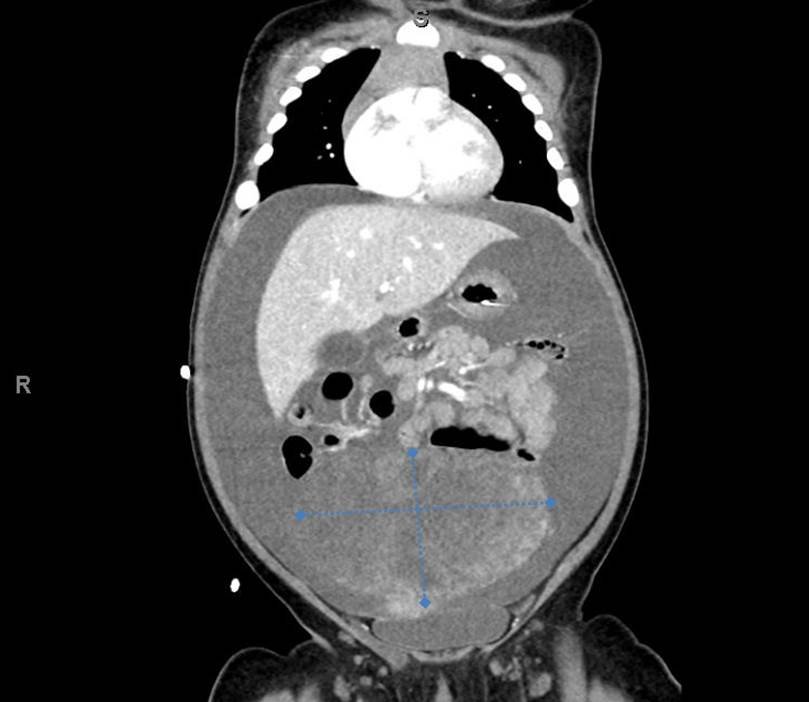

A 5-month-old female presented to the emergency department with worsening abdominal distention and postprandial emesis. Point-of-care ultrasound (POCUS) demonstrated extensive abdominal free fluid with a large, heterogeneous mass in the suprapubic region. This was confirmed on computed tomography (CT) of the abdomen and pelvis. The patient was urgently taken to the operating room for exploratory laparotomy where a ruptured tumor was discovered. The patient was eventually diagnosed with ovarian juvenile granulosa cell tumor. POCUS can be vital in guiding the recognition of rare pediatric conditions in the emergency department and should be considered in patients where there is concern for an acute abdomen.